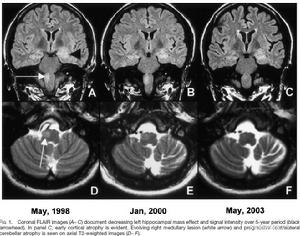

小腦蚓部SPECT顯示小腦局部腦血流(rCBF)明顯減少,但rCBF降低程度與MRI顯示的小腦萎縮程度不一致。PET檢測除小腦半球、小腦蚓部和腦幹外,枕部皮質也有明顯的局限性低代謝。